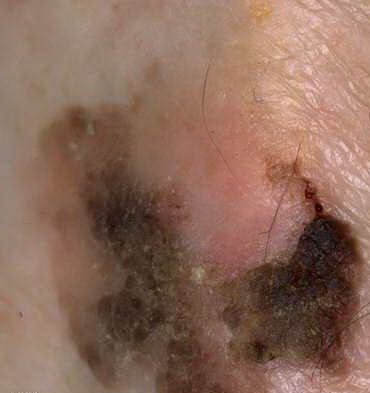

Seborrheic keratoses = التقران الدهني